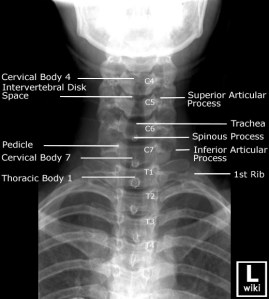

Image source from WikiRadiography (Wetpaint) here.